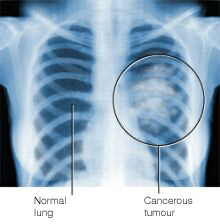

Dr. Donald Tashkin, a los angelesi egyetem (UCLA) professzora a marihuána tüdőre gyakorolt hatásainak egyik legelismertebb szakértője. Az amerikai kormány által támogatott kutatásaira széles körben hivatkoznak a drogprevenciós szóróanyagok. Tashkin és kollégái kimutatták a marihuána-füst karcinogén (rákkeltő) elemeit, amelyek a dohányfüsthöz hasonló kockázatot jelentenek a tüdőre. Bár kizárólag a marihuána-füst hosszú távú, intenzív belélegzése miatt kialakult rákos daganatot még nem sikerült kimutatniuk, találtak olyan rosszindulatú sejtburjánzásokra utaló nyomokat, amelyek idővel daganatot is képezhetnek. Tashkin maga hosszú időn keresztül képviselte azt az álláspontot, hogy a kannabisz füstje tüdőrákot okozhat.

A los angelesi rákszűrő program keretében az elmúlt években Tashkinék kiterjedt vizsgálatot folytattak ennek a hipotézisnek az igazolására. 1209 rákos beteg (611 tüdőrák, 403 szájrák, 90 gégerák, 108 nyelőcsőrák) körében kérdőívek segítségével mérték fel a marihuána-használat mértékét. A betegek 46%-a soha nem használt marihuánát, 31%-uk egy évnél ritkábban, 12%-uk 10-20 jointot fogyasztott egy évben, 2%-uk évente 30-60 jointot, 3%-uk évente több mint 60 jointot szívott. Tashkin az az egyéb befolyásoló tényezők (dohányzás, ivászat, egyéb drogok, genetika, szocio-demográfiai tényezők stb.) kontrollálása után megállapította a marihuána relatív rákkeltő potenciálját, és arra a meglepő eredményre jutott, hogy míg a dohányzás egyértelmű rizikófaktornak bizonyult, a marihuána nem növelte számottevően a rák kialakulásának kockázatát. Sőt, azoknál a pácienseknél, akik kizárólag marihuánát szívtak és nem dohányoztak, még pozitívabb eredményeket kaptak, mint a sem nem dohányzó, sem füvet nem szívó kontroll-csoport tagjainál!